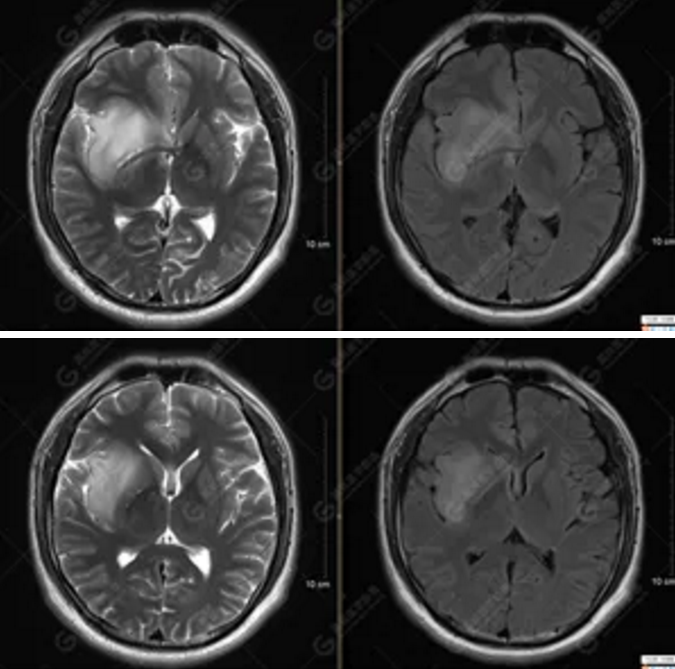

圖1為多體素MRS檢查,感興趣區(qū)為正常腦組織的MRS表現(xiàn)。圖2為單體素MRS,右側(cè)顳葉病灶內(nèi)NAA峰明顯下降,Cho峰明顯升高,NAA/Cr值為0.1,Cho/Cr值為3.64。